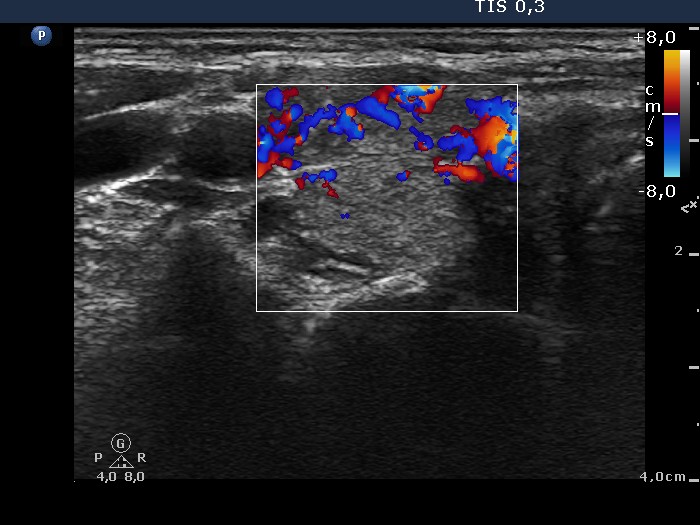

Graves' disease - Case 1049

Follow-up investigation 33 months after first visit (ultrasonographic picture 3)

Patient on daily 20 mg methimazole therapy in euthyroid state

Right lobe, transverse scan, color Doppler mode. The vascularization is already more pronounced than the average but compared with previous investigation, it is decreased.